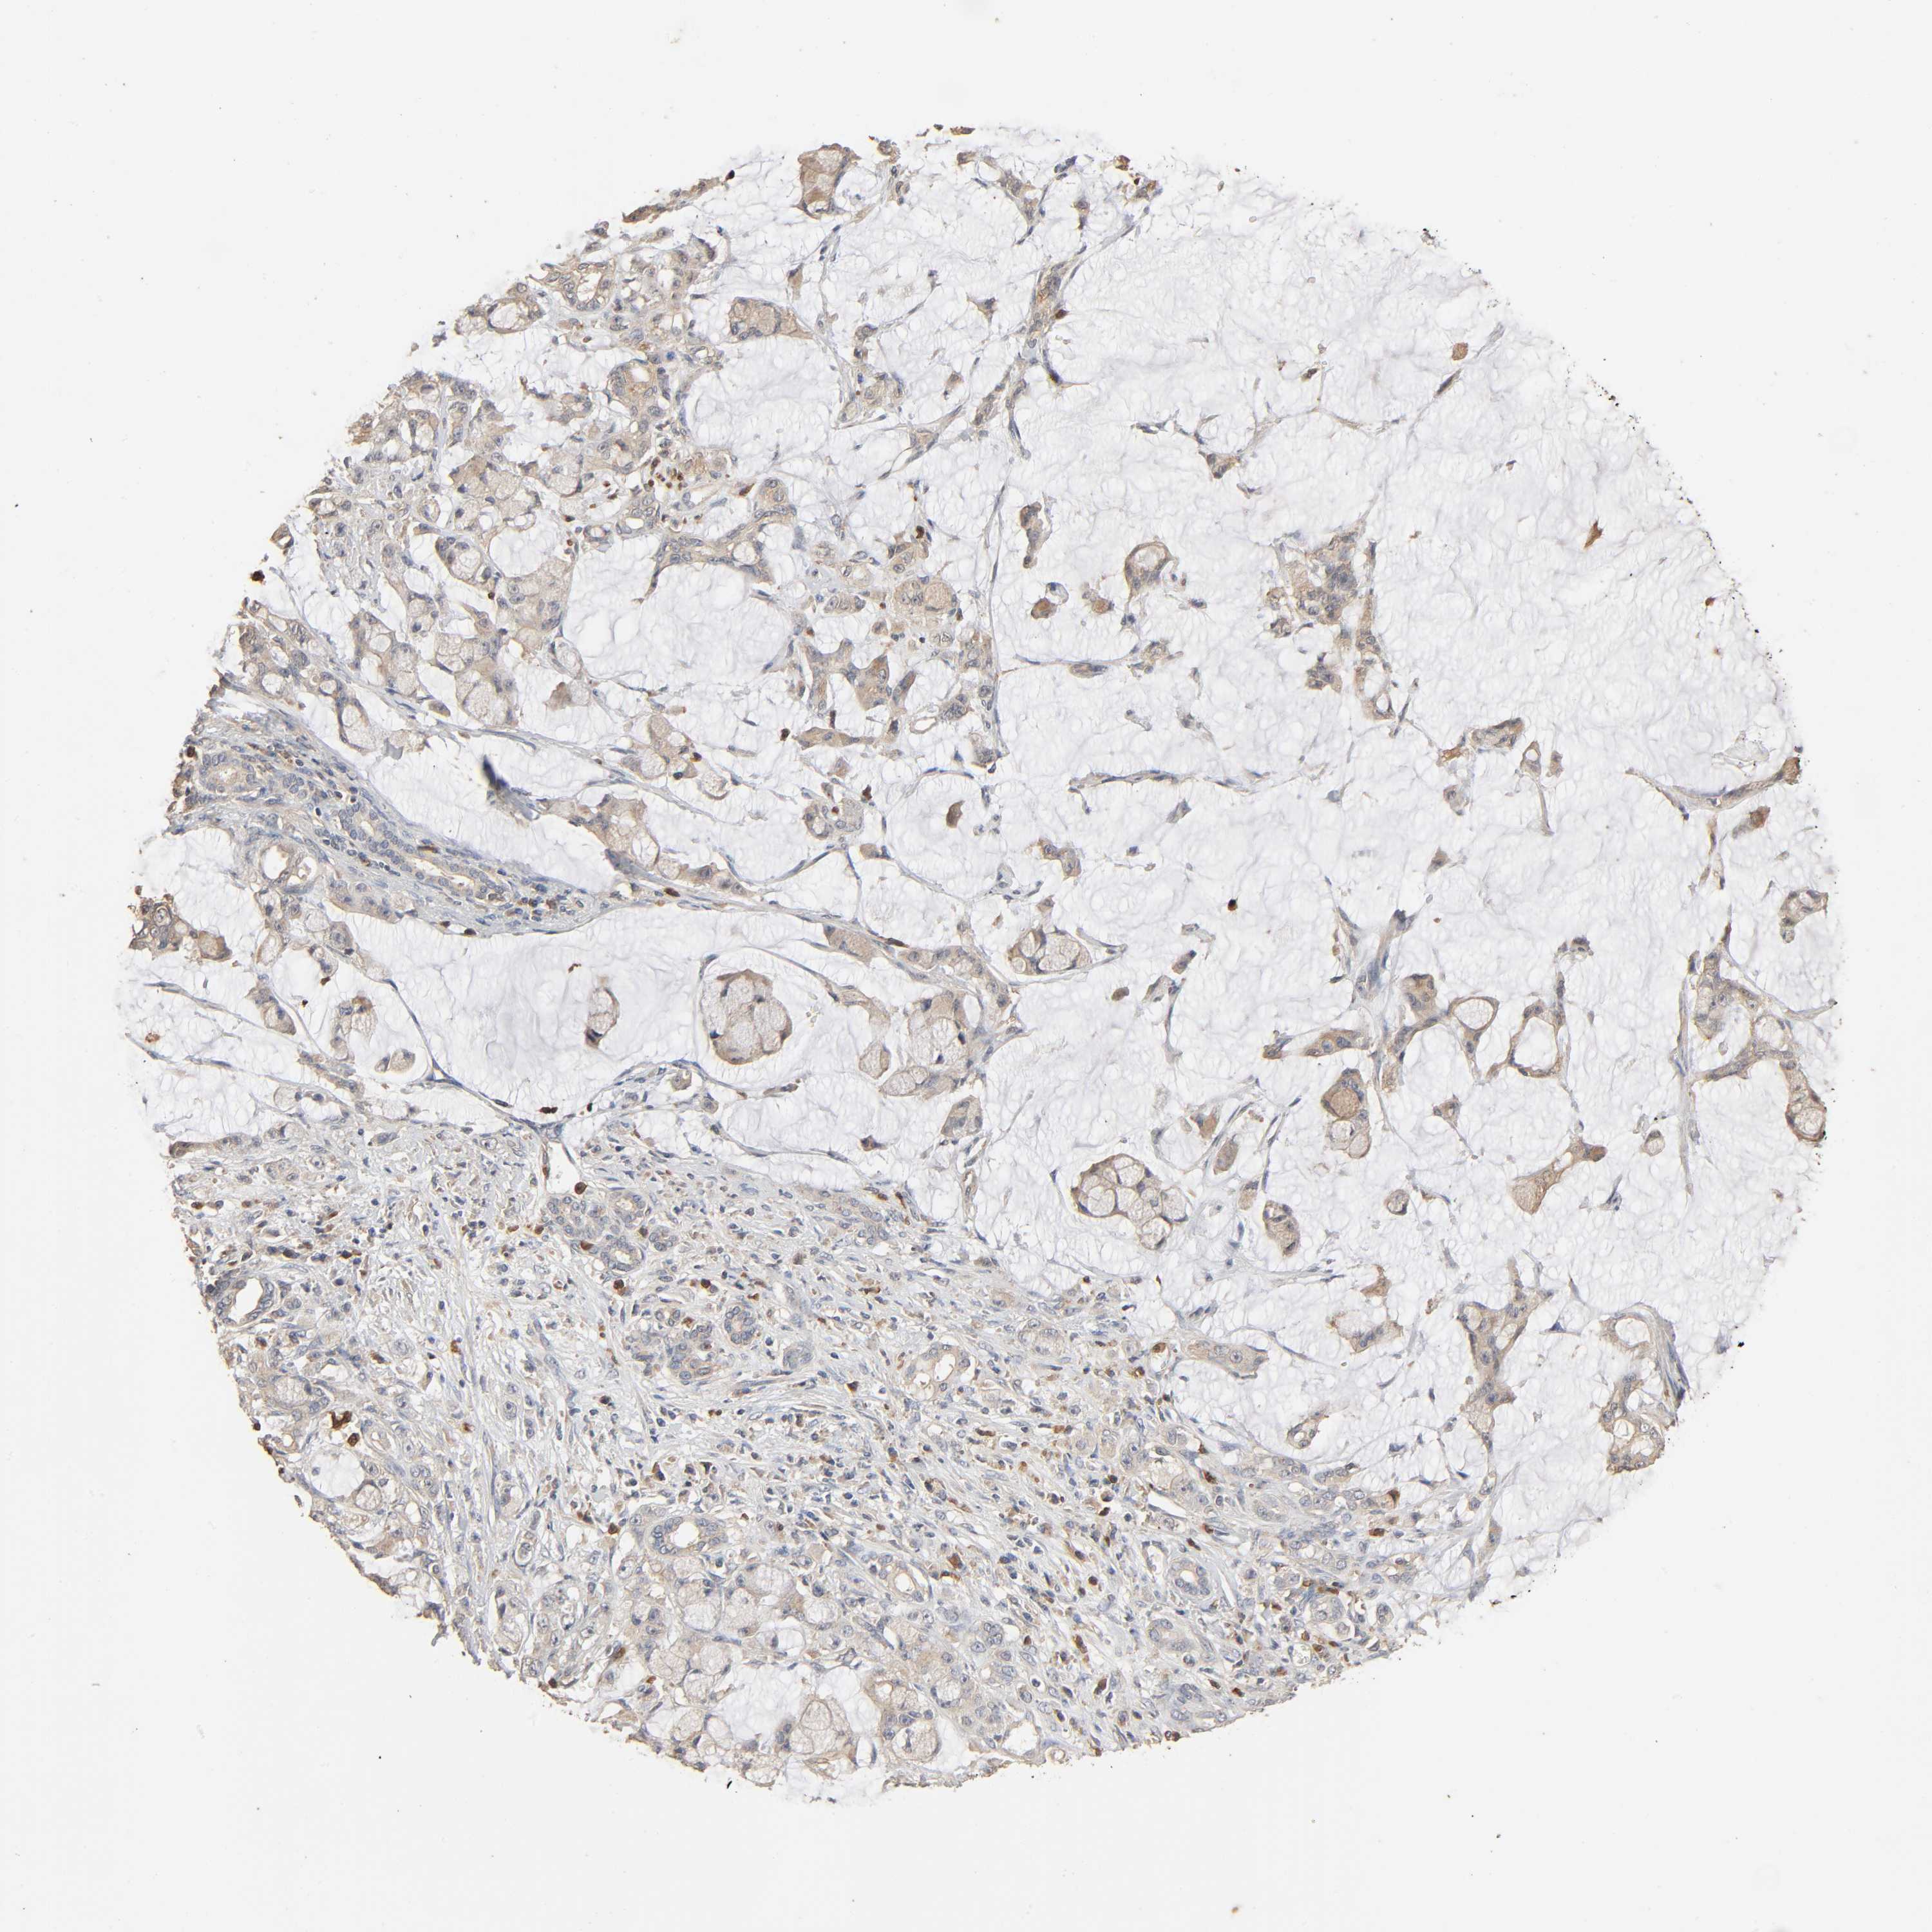

PANCREATIC CANCER - Protein expressioni

A mouse-over function shows sample information and annotation data. Click on an image to view it in a full screen mode. Samples can be filtered based on level of antibody staining by selecting one or several of the following categories: high, medium, low and not detected. The assay and annotation is described here.

Note that samples used for immunohistochemistry by the Human Protein Atlas do not correspond to samples in the TCGA dataset.

Antibody stainingi

Antibody staining in the annotated cell types in the current human tissue is reported as not detected, low, medium, or high, based on conventional immunohistochemistry profiling in selected tissues. This score is based on the combination of the staining intensity and fraction of stained cells.

Each image is clickable and will lead to virtual microscopy that enables deeper exploration of all samples and also displays staining intensity scores, fraction scores and subcellular localization as well as patient and tissue information for each sample.

Antibody HPA000962

Antibody HPA004119

Staining

High

Medium

Low

Not detected

Intensity

Strong

Moderate

Weak

Negative

Quantity

>75%

75%-25%

<25%

None

Location

Nuclear

Cytoplasmic/membranous

Cytoplasmic/membranous,nuclear

Adenocarcinoma, NOS

Adenocarcinoma, metastatic, NOS